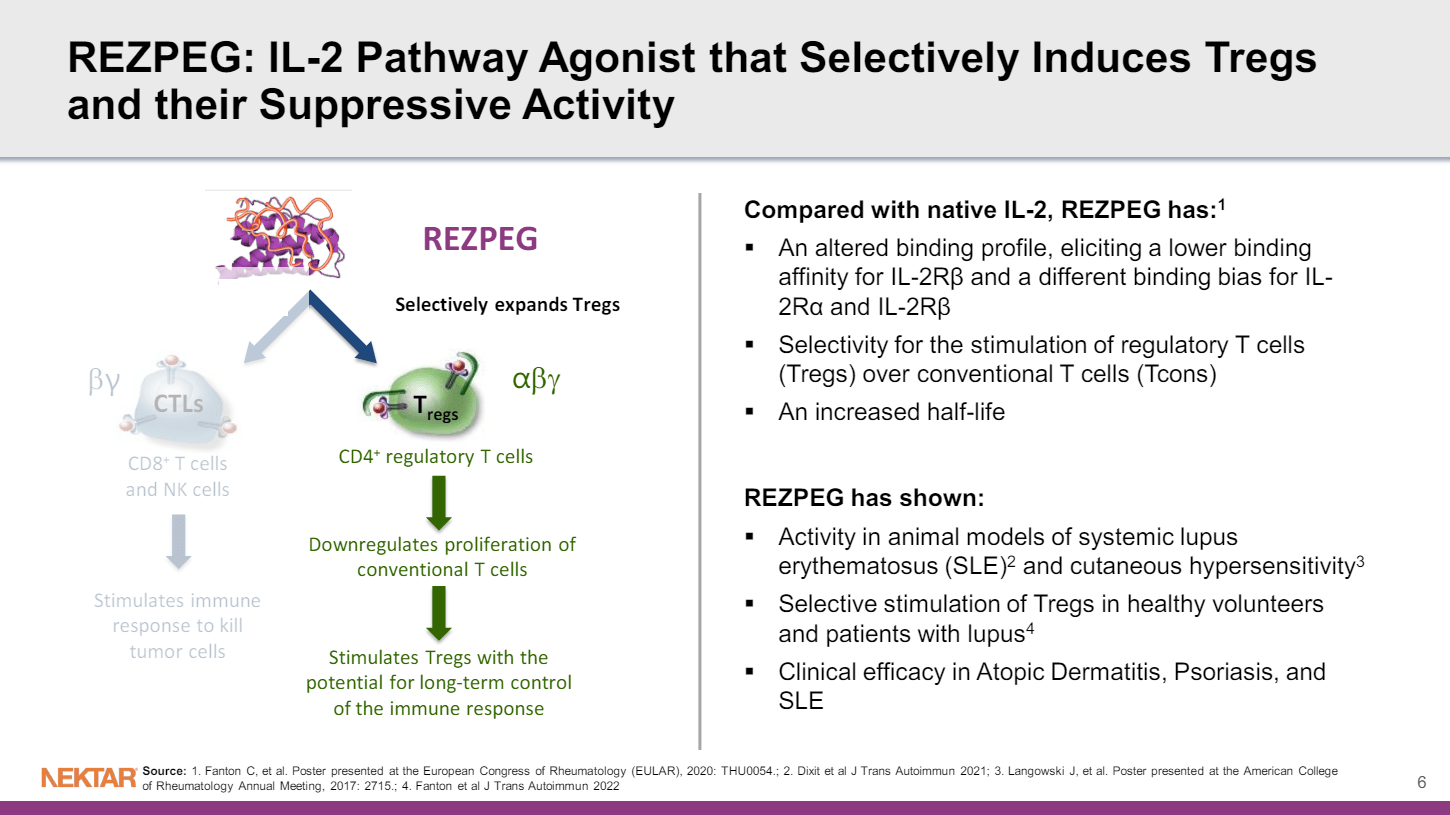

查看详情 Rezpegaldesleukin 可快速用于治疗严重至极严重斑秃

Rezpegaldesleukin 可快速用于治疗严重至极严重斑秃

美国食品药品监督管理局 (FDA) 已授予 rezpegaldesleukin 快速通道资格,用于治疗成人和 12 岁及以上、体重至少 40 公斤的...